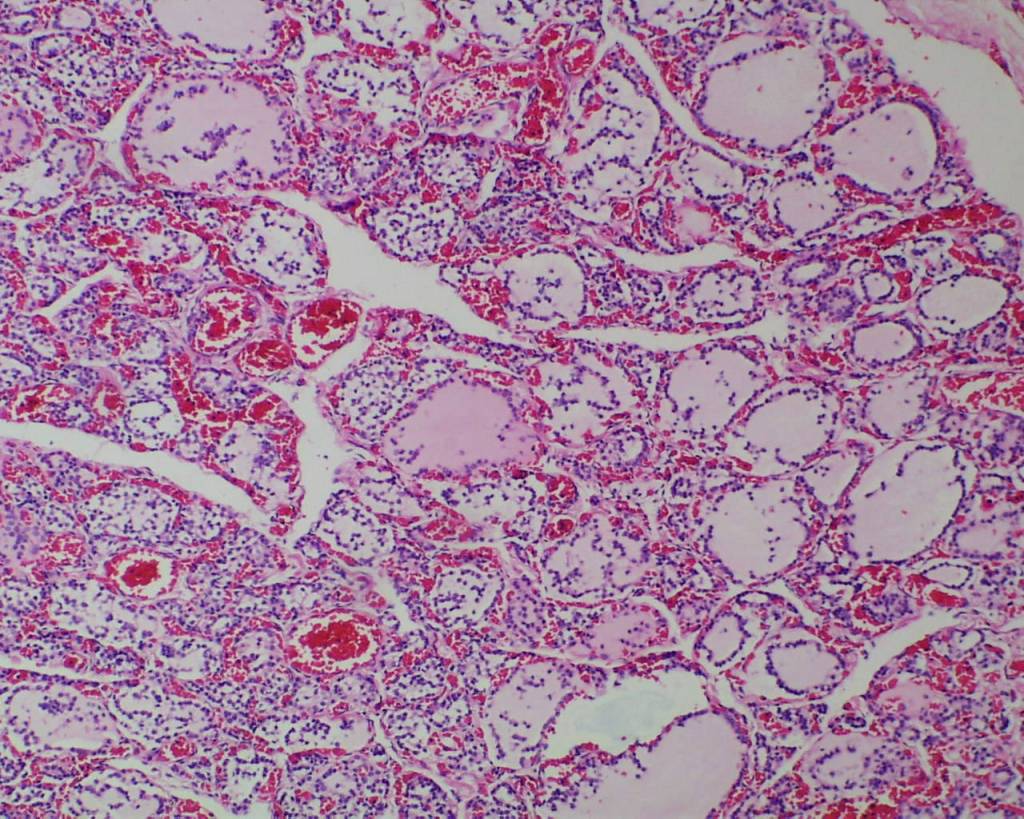

Colloid in follicles: Temperature modulation in utero is to a large extent controlled by the mother’s body’s temperature. The developing thyroid does accumulate iodinated protein within variable size follicles. Circulating thyroid hormone in the fetus is mostly reverse T4 which prevents overheating of the fetus in the body-temperature water bath of amniotic fluid. TSH is produced in the fetal hypothalamus and placenta at a basal rate. However, with birth, there is TSH surge that results in release of active thyroid T3 and T4 that initiates necessary thermogenesis in the fetus3. This surge occurs within the first 15 minutes. In the sheep, if a lamb is delivered but the attachment of the umbilical cord remains functional to the placenta, the externalized lamb will become hypothermic. Cutting the cord initiates the surge of TSH and epinephrine necessary to maintain body temperature outside the womb.

This histology of loss of follicular colloid in the 24 to 48 hours after birth has been documented in newborn infants at autopsy4 (Fig 3a-c).

In stillborn infants the extent of colloid in the thyroid follicles and mononuclear cells in the follicles varies. Some variability may be due to gestational age differences (Fig 4a, b).

Another variable may be the effect of autolysis, but this has not been carefully correlated with postmortem retention intervals. Correlations of thyroid histology with disease in the newborn infant has been studied5. There is not a study correlating the changes in colloid with other findings in stillbirth, such as evidence of acute asphyxia or thymic involution.